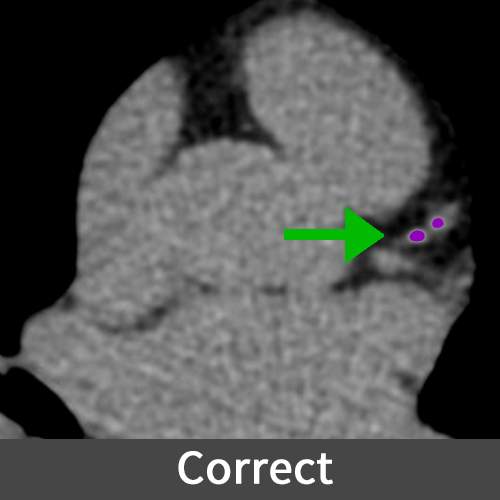

Calcium Score

A calcium score, determined through a cardiac CT scan, quantifies the amount of calcium in the coronary arteries, serving as an indicator of coronary artery disease and helping assess the risk of future heart problems. Higher scores indicate a greater plaque burden and an increased risk of heart disease, aiding doctors in treatment decision-making.

Missing calcified regions in a report can lead to an underestimation of coronary artery disease severity, potentially delaying necessary treatments and increasing the risk of heart-related complications for the patient.

Figure E (Right): Incorrect and correct markings of the calcium used for the Calcium Score evaluation.